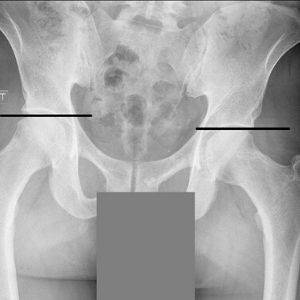

You won’t be left guessing about your health. We start with a detailed consultation & physical exam, but the real difference is in our comprehensive digital X-rays. You'll see exactly what’s going on: where the spine is misaligned, how severe it is, and why you feel the way you do. Instead of vague explanations or guesswork, you’ll get clear answers that finally make sense of your symptoms & show the best path moving forward.

Taking action as soon as possible can make all the difference in how quickly you see results and how much you can expect to change with your chiropractic adjustments and your posture-improving efforts. Spinal degeneration is a permanent change to your spine, but it does take years to build up. Once you've started to see evidence on x-ray, it's progressed and you shouldn't wait anymore.

At CORE Chiropractic, we utilize several adjusting techniques to help you get the best, most comfortable results possible. We take spinal x-rays to make sure you don't have any underlying conditions that will stop us from working on you, but also to establish a baseline as to where you are at the beginning of care. Later we can do follow up x-rays to show you how much has improved.